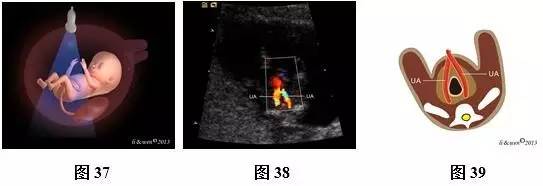

超声扫查方法:声束通过胎儿上腹部的胃泡、肝脏横断扫查(图31),可获得上腹部横切面图(图32,33),然后声束平面向胎儿尾侧平移扫查,通过脐带腹壁插入口时(图34),可获得脐带腹壁插入口横切面(图35,36)。通过膀胱时(图37),可即获得膀胱水平横切面(图38,39)。

标准切面判断标准:腹部呈圆或椭圆形,脊柱为横切面,上腹部横切面可见正常胃泡位于左侧,肝脏位于右侧;脐带腹壁插入口横切面可见脐带腹壁入口位于前腹壁中央,与后腹壁脊柱回声连成一直线构成此平面的前后中轴线;膀胱水平横切面彩色多普勒可见膀胱位于盆腔内,呈无回声,在膀胱的两侧各有1根脐动脉,略向脐孔处旋转探头,可见脐血管在腹正中处进入脐带内。

主要观察的内容:(1)上腹部横切面:主要观察内容是胃泡及肝脏位置、大小。正常胃泡位于腹腔左侧,肝脏位于腹腔右侧。(2)脐带腹壁插入口横切面:腹壁完整性与连续性,脐带腹壁入口处位置是否正常、有无包或肠管外翻等。(3)膀胱水平横切面彩色多普勒:观察脐动脉数目,膀胱位置、大小及壁的厚度等。

注:ST为胃泡;LIVER为肝脏;SP为脊柱;IVC为下腔静脉;AO为腹主动脉;UA为脐动脉;L为左侧;R为右侧;

图31~39 11~13+6孕周胎儿腹部扫查方法、声像图及模式图。图31上腹部横切面图扫查模式图;图32、33上腹部横切面图声像图及模式图;图34脐带腹壁插入口横切面扫查模式图;图35、36脐带腹壁插入口横切面声像图及模式图(黑色箭头示脐带腹壁入口);图37膀胱水平横切面扫查模式图;图38、39膀胱水平横切面彩色多普勒。